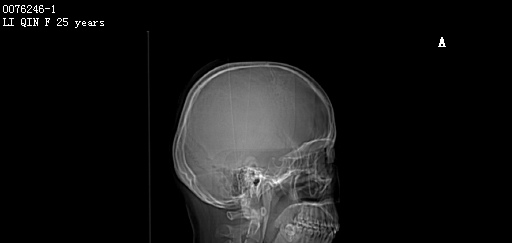

CT50997:F,25y。头部外伤1天。

女,25岁。头部外伤1天。 临床诊断:头部外伤。 今行头部CT检查,图像如下:

考虑右侧侧脑室体部旁脑灰质异位;建议行MRI检查进一步明确诊断。

两侧侧脑室体部似见灰质密度影,提示脑灰质移位可能,建议MRI检查。

右侧侧脑室旁脑灰质异位?左侧侧脑室旁也显示一点,尾状核体部影像,建议MRI

考虑右侧侧脑室体部旁脑灰质异位;不除外尾状核体部,建议行MRI检查进一步明确诊断。